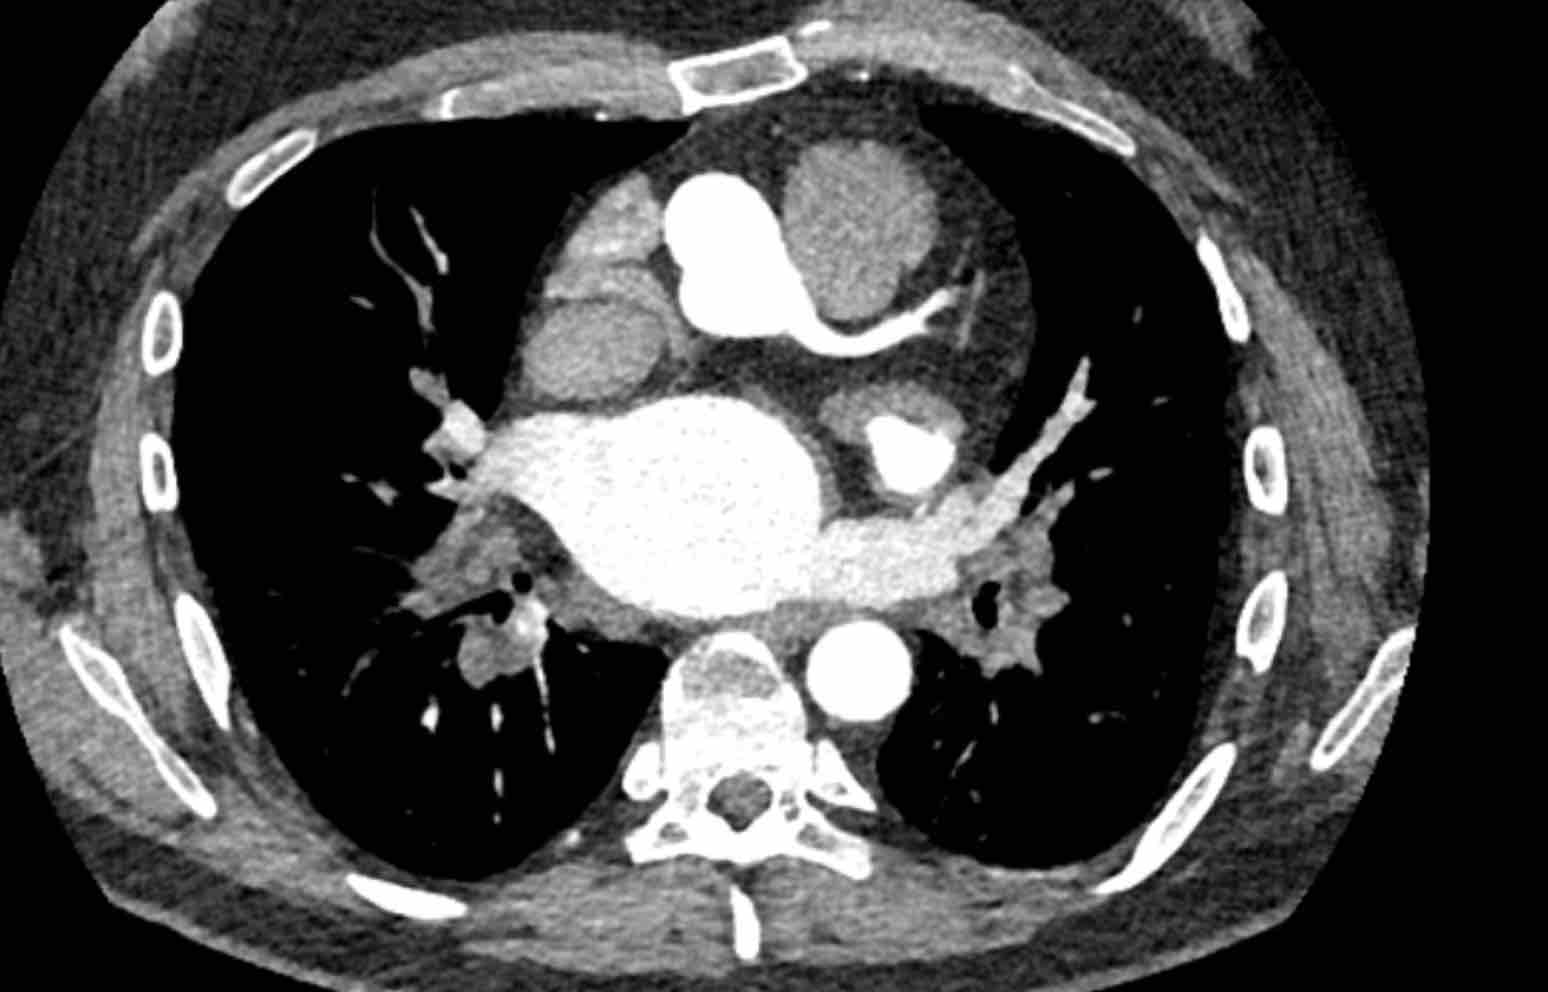

Hình ảnh

Khiếm khuyết tưới máu trong vùng tưới máu của LAD ở bệnh nhân chấn thương 45 tuổi, nhập viện sau khi ngã cầu thang trong lúc khuân vác nặng.

Cài đặt cửa sổ sắc nét hơn giúp đánh giá sự khác biệt tỷ trọng cơ tim.